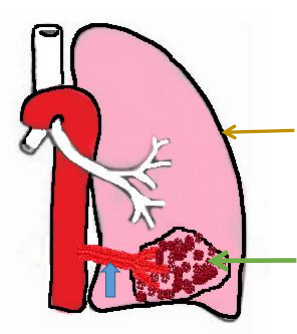

左肺及气管、主动脉正常位置和形态

左肺异常血管(蓝色箭头)所供血的异常肺组织——隔离肺(绿色箭头)